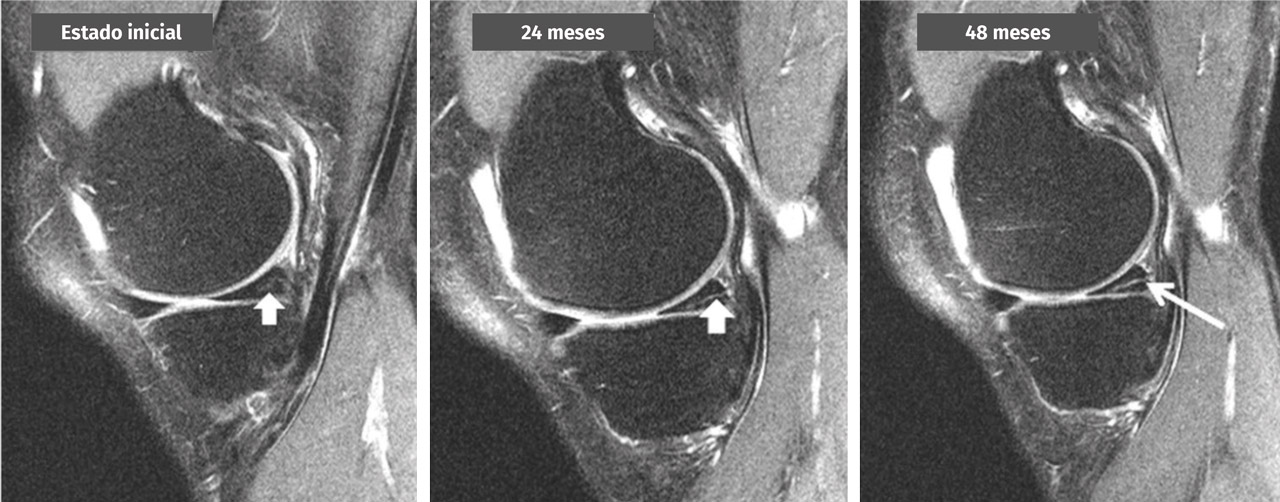

Figura 2. Transformación de una señal intrameniscal en una lesión horizontal en el cuerno posterior del menisco interno a lo largo de 4 años observada en una secuencia de resonancia magnética de rodilla de 3 teslas (cortesía de M. Englund).

¿Qué hallazgos sugieren la presencia de una lesión degenerativa del menisco en una resonancia magnética?

En RM, la lesión degenerativa del menisco normalmente se caracteriza por una señal intrameniscal que incluye un componente horizontal, que a menudo exhibe una comunicación con la superficie inferior del menisco en al menos 2 cortes de la RM. No obstante, también pueden darse patrones de rotura más complejos con múltiples configuraciones. La localización más habitual de una lesión degenerativa del menisco es el cuerpo y/o el cuerno posterior del menisco interno (grado B).